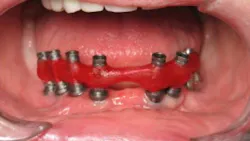

To ensure that your final screw-retained framework has the optimum passive seat, a verification jig (figure 1) is recommended. A verification jig is used to verify that the master model is accurate prior to manufacturing the framework.

The jig consists of temporary cylinders luted together with a rigid resin material and sometimes thick wire or rods. The purpose of the verification jig is to mimic the final frame in fit. To verify the accuracy of the model, place the jig on the model and in the mouth.

Place the jig on top of all of the implants in the mouth. Look for any sign of a rock in the frame. Screw in the most distal screw, and look to see if the frame lifts on the other side. Remove the screw and do the same on the most distal implant on the other side. Continue with this procedure until every screw has been tried in and no lifts are seen.

If you find no rocks, the model is accurate to the mouth. If the jig rocks anywhere, section the frame and relute it in the mouth until it seats passively without any rocks. The lab will then modify the master model with the jig, and the next step can begin.